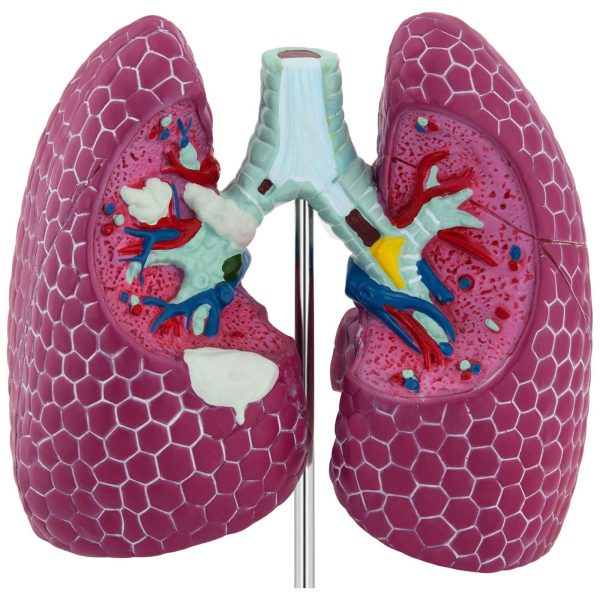

Cilvēka plaušu ar bojājumiem 3D anatomiskais modelis

Model anatomiczny chorych płuc marki Physa pozwoli dokładnie zobrazować m.in. nowotwór układu oddechowego człowieka. Szczegółowość wykonania umożliwia pokazanie wszystkich detali płuc. Dzięki temu zaprezentujesz różnice między chorym a zdrowym organem. Model wykonany z tworzywa PVC.

- – Model 3D chorych płuc,

- – Tworzywo PVC,

- – Podstawa zabezpieczająca model.

Parametry techniczne:

- – Model – PHY-LM-1

- – Materiał – PVC

- – Wymiary (DxSxW) – 11 x 14 x 20 cm

- – Waga – 0,55 kg

W zestawie:

- – Model chorych płuc,

- – Plakat,

- – Podstawa,

- – Instrukcja obsługi.